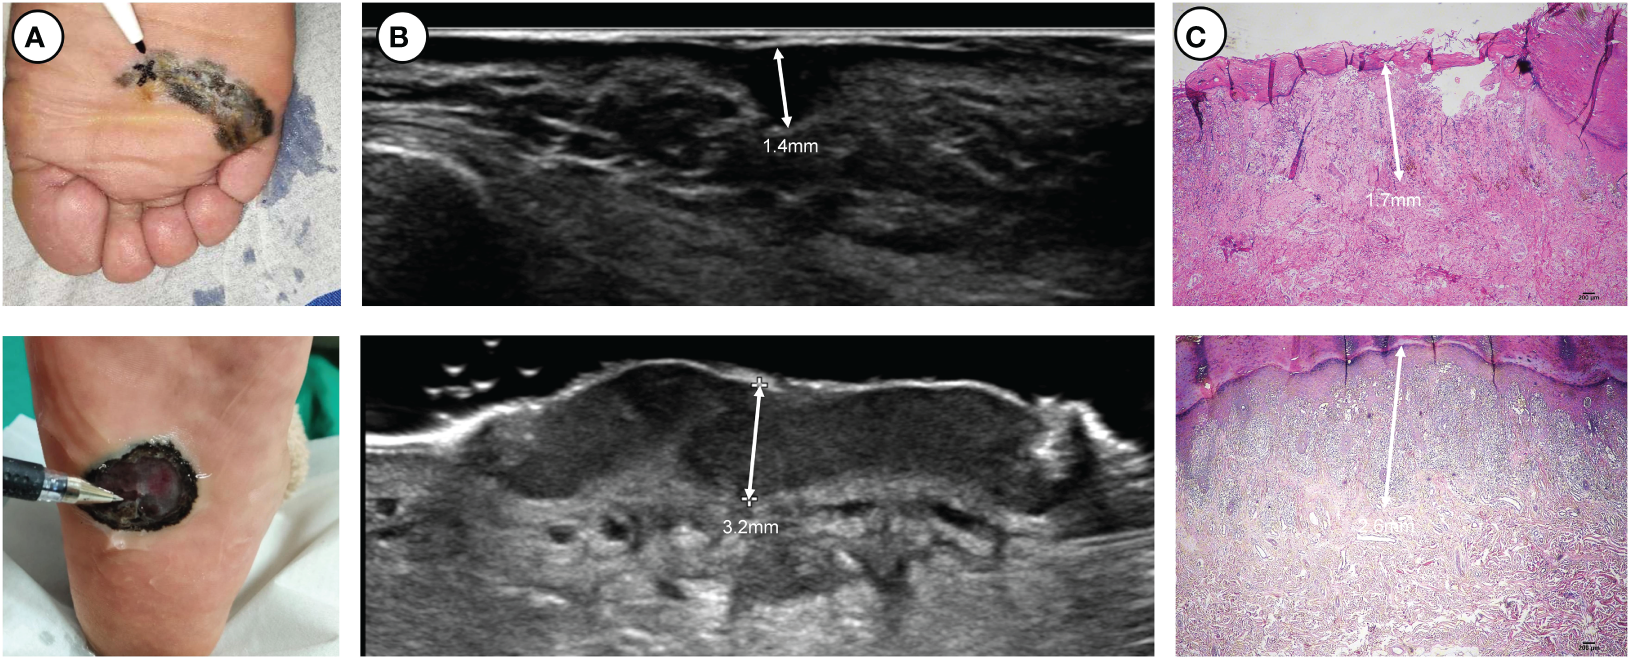

A 5-18 MHz linear transducer (Philips, EPIQ5, 5-18 MHz, MSK Superficial) was used to examine the lesions. The width of the probe was 38 mm with a maximal depth of 60 mm. Standard sonographic gel was applied to separate the probe face from the skin surface. The probe was held manually and moved at least two directions over the skin to provide screening of the entire lesion. Two sonologists with over five years of experience independently scanned the lesion, performed multiple measurements for the thickest area of suspiciousness, and recorded the maximum thickness (Figure 1; Figure S1).

Figure 1

Two thick ulcerated nodular melanomas located on the plantar side: (A) clinical pictures, (B) ultrasound pictures and (C) pathological pictures. At the apex of the pen lies the location where ultrasonic measurements exhibit the maximum thickness.